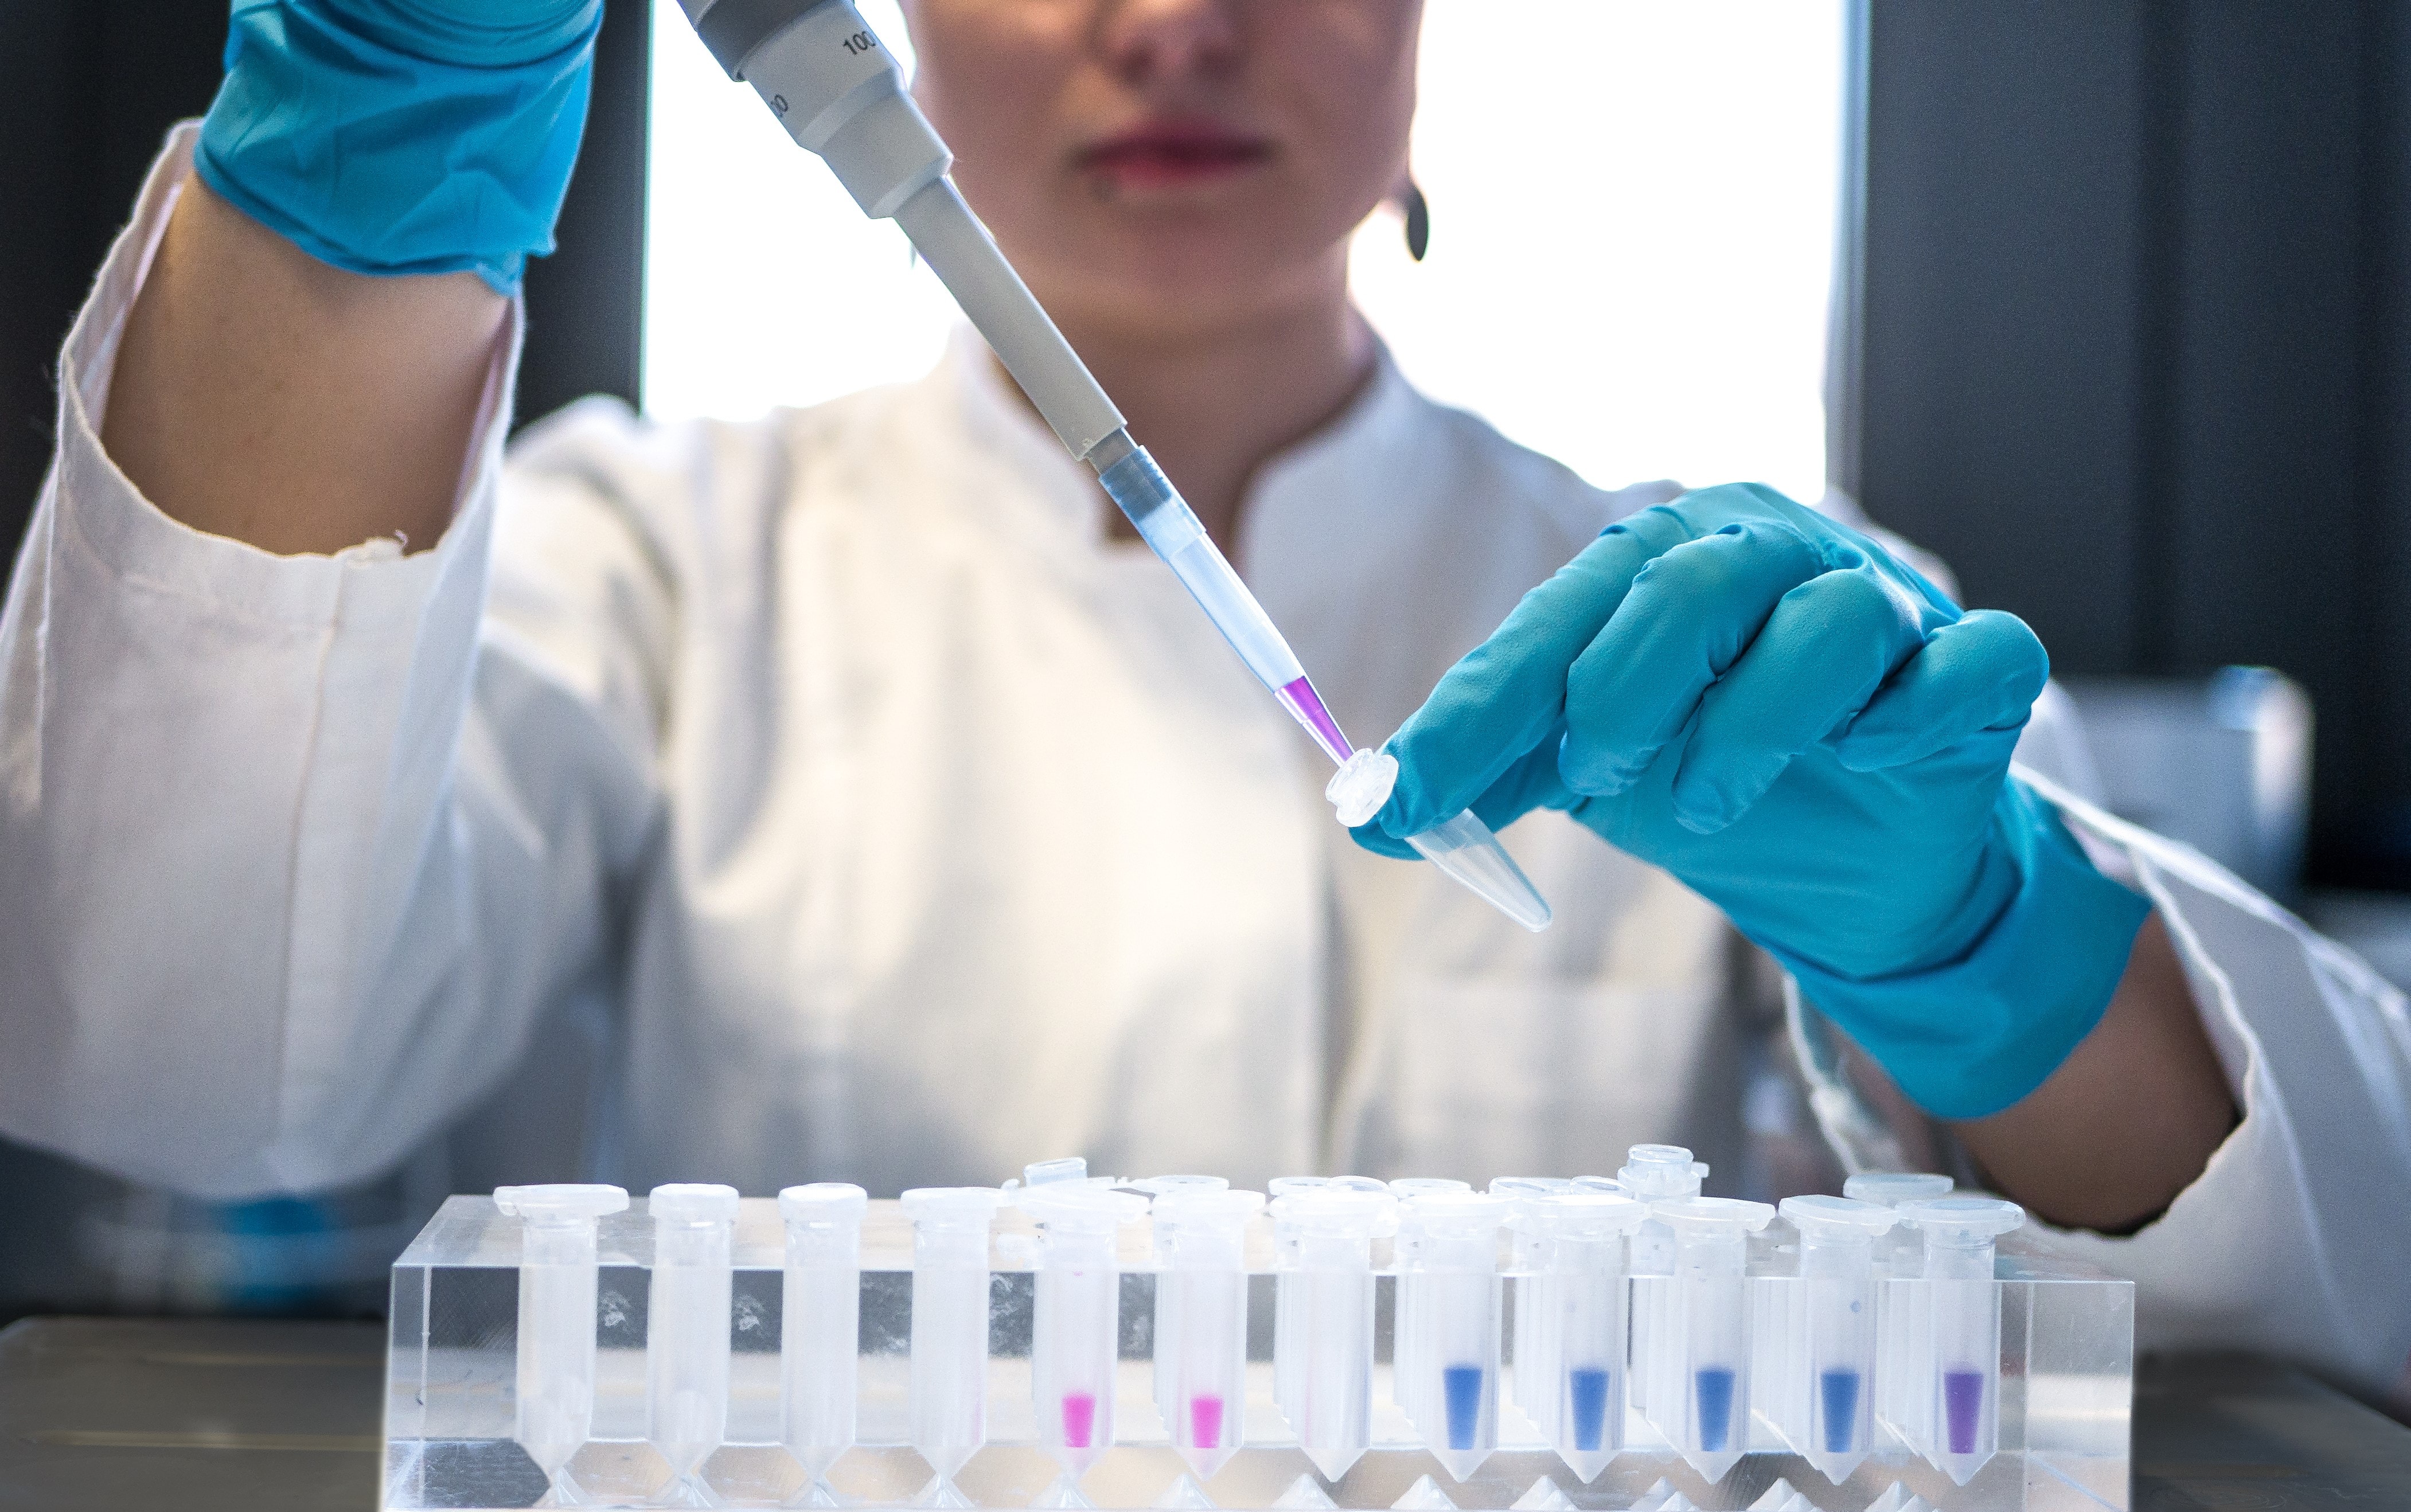

BioQuant is Heidelberg University's interdisciplinary Research Center for Quantitative Analysis of Molecular and Cellular Systems. The center is regarded as a hub for research and teaching in quantitative biology. Work at BioQuant integrates quantitative experimentation, cutting-edge technology and computing to advance an integrative understanding of the complexity of the systems studied. Such "cross-boundary" research is timely and has become necessary for answering numerous questions in biological and medical systems. And it has been part of BioQuant's mission since its inception, and the environment at BioQuant fosters such activities on campus and beyond with unsurpassed opportunities.